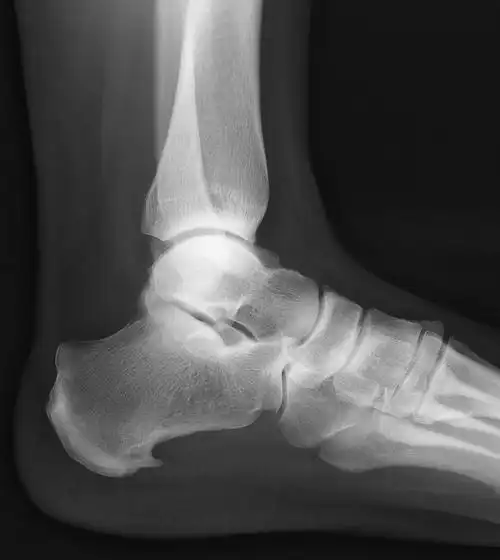

跟骨骨刺

左脚x光片显示跟骨刺呈红色.